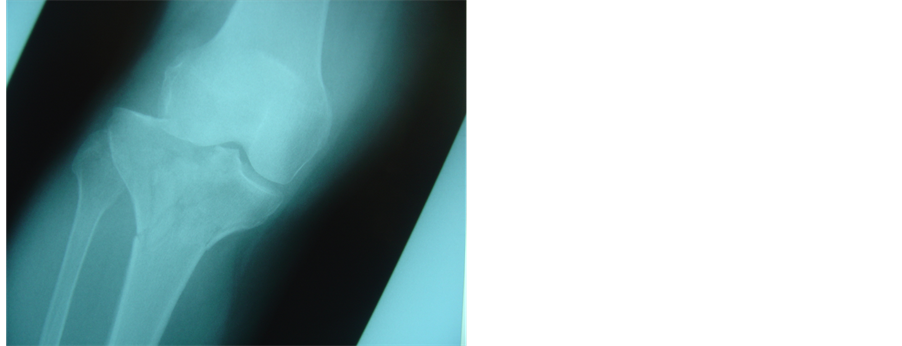

Figure 2. (a), (b): Schatzker IV fracture. Pre operative X-rays AP and Lateral; (c), (d): The fracture was treated with combination of hybrid fixator with one canulated screw. X-rays AP and Lateral three years later before removal of canulated screw.

Operation was performed under epidural anesthesia. Preoperative assessment of radiographs and computerized tomography scans helped us achieve a good perspective of the fracture components. A tourniquet was applied only if the open method was to be used. Initially, when necessary, the knee hematoma was aspirated. Operation was then carried out under II control and always started with the application of one or more 6.5 millimeter canulated screws with washers, usually from the lateral side, parallel and as close to the articular surface as possible. At this stage, if needed, the articular surface was elevated by the use of a guide pin. Thus, the tibial plateau were reduced and compressed. Fixation was then completed with application of a hybrid external fixator (bridging the knee if required) or less invasive internal fixation with a limited lateral approach and an anatomic locking plate. Manual traction and various instruments (an owl or a large tenaculum reduction forceps or a tractor or use of a k-w like a joystick) were used to reduce the condyles [6] . Varus or valgus angulation was assessed very carefully and corrected. We did not perform ligament or meniscus repairs. All fractures were reduced with the knee closed. In case of instability, the knee was bridged with an extension of the hybrid to the lateral side of the femur [7] . We used a full ring, parallel to the articular surface and centered over the tibia, allowing close to 90˚ of knee flexion. We always applied two wires forming an x in axial viewing. These wires were placed within anatomically safe zones at the typical positions (posterolateral to anteromedial tibia through the head of the fibula and anterolateral to posteromedial). Then a third wire was inserted, usually between the first two and parallel to the articular surface in the AP view, but occasionally parallel and above the second one.. If an olive wire were used, it was inserted until the olive contacted the bone surface to apply extra compression. The wires were then fixed to the ring and tensioned. Three peripheral pins were applied, the fixator mounted and the fracture finally manipulated, reduced and stabilized (Figures 1(a)-1(d), Figures 2(a)-2(d)).